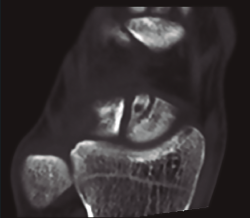

En cuanto al diagnóstico, la controversia reside en cuándo y qué pruebas complementarias realizar en las sospechas clínicas de fractura sin una imagen de radiología concluyente. A menudo las fracturas agudas pasan desapercibidas; la sensibilidad de la radiología va del 84 al 98%(1), la resonancia magnética nuclear (RMN) puede ser útil, con una sensibilidad superior al 95%, pero con una especificidad inferior(2), siendo la tomografía computarizada (TC) la más sensible y especifica(3)(Figura 1).

Figura 1. Imagen de fractura no desplazada de escafoides en tomografía computarizada.